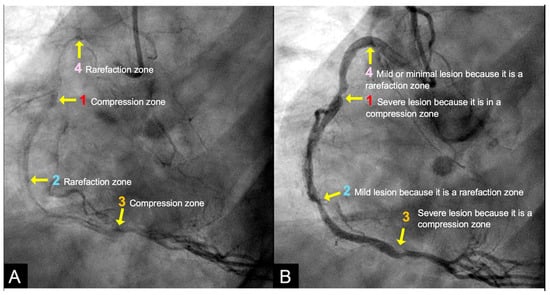

Acoustic Investigations. Once the boundary conditions and flow dynamics in coronary arteries were established through simulations replicating analogous processes in pipes, the investigation shifted to analyzing pressure wave reflections [7]. To explore this phenomenon, acoustic principles were incorporated to examine flows propagating near the speed of sound in both pipes and coronary arteries. Building on the principles of sound wave propagation—where particle displacement creates alternating zones of compression and rarefaction—we hypothesized that these acoustic phenomena could be applied to coronary angiograms to delineate distinct zones of high-intensity contrast (compression zones, also called as antinodes), moderate-density contrast (rarefaction zones, also categorized as antinodes), and minimal contrast concentration (nodes). These zones of contrast concentration were interpreted as surrogates for varying pressure surge intensities capable of damaging the arterial intima. The antinodes were subsequently analyzed for their potential association with lesion development and progression, while the nodes were examined as regions exhibiting minimal or absent lesions [8]. The goals of the investigation of coronary flow dynamics based on acoustics practice are listed in Figure 4 and Table 2.

IN VIVO Coronary Flow Analysis. Angiographic Compression and Rarefaction Zones. Building on an advanced understanding of pressure wave reflections in pipes from an acoustic perspective, this investigation applied acoustic principles to analyze flow dynamics in coronary arteries. The primary objective was to delineate and quantify regions within the coronary arteries characterized by pockets of high-contrast density (compression) and moderate-contrast density (rarefaction), identified as antinodes (Figure 15A,B). Conversely, areas with minimal contrast were designated as nodes. These classifications were finalized at the end of the second cardiac cycle when the contrast was almost all washed out, leaving pockets of contrast which most likely were zones of compression or rarefaction (labeled as antinodes). The needs for identifying the five zones of compression and rarefaction (antinodes) and the minimal or lesion-free segments (nodes) within a coronary artery are listed in Table 4.

The secondary objective was to examine the relationship between antinodes and the presence of coronary stenoses, as well as between nodes and minimally diseased or lesion-free coronary segments. Ultimately, the investigation aimed to establish antinodes as potential markers for high-pressure surges linked to intimal damage. These locations of antinodes are used to construct a coronary acoustic activity (or action) map, enabling the identification of existing lesions, forecasting the progression of current lesions, and predicting the development of potential future lesions. Table 5 outlines the protocol on how to identify and label the five zones of compression and rarefaction (antinodes) and the minimal or lesion-free segments (nodes) within the coronary arteries. The protocol to identify the antinodes of compression and rarefaction and the nodes in between the antinodes uses the novel coronary dynamic angiographic technique. The protocol is listed in Table 5 and Figure 16A–E.

CRITICAL THINKING. High Concentration of Contrast at location 1 as a Marker of Compression Activity. During a typical cardiac cycle, antegrade blood flow accelerates during diastole and transitions rapidly into the systole, initiating a water hammer phenomenon that generates a retrograde pressure wave. This retrograde wave propagates at nearly the speed of sound and undergoes multiple reflections within one or two diastole–systole cycles along the length of a coronary artery. These reflections produce hundreds of retrograde pressure waves, which may synchronize with antegrade waves to form resonant patterns or, conversely, cancel out. The wave reflections occur at distinct locations: the diastole-to-systole junction (location 1), the coronary artery ostium (location 4), and the systole-to-diastole junction (location 2). The resulting wave dynamics display features of acoustic resonance, with regions of high contrast concentration corresponding to antinodes—pressure peaks associated with arterial damage or the progression of atherosclerosis (Figure 16E). High-contrast regions at locations 1 and 4, observed in coronary angiography, likely represent zones of compression and rarefaction, indicative of pressure surges that may compromise the intimal layer. The critical challenge lies in determining how these observations and hypotheses can be rigorously validated.

CRITICAL THINKINGS. Pressure Surge and Mechanism of Damage. When a pressure wave propagates through the blood of a coronary artery, it generates alternating regions of particle compression and rarefaction. At compression points (e.g., locations 1 and 3), there is a high concentration of contrast, whereas at rarefaction points (e.g., locations 2 and 4), the contrast concentration is less intense.

At location 1 with compression, corresponding to a pressure crest, the low-pressure antegrade flow during diastole is rapidly overtaken by a high-pressure surge during systole, producing a pronounced pressure peak. This abrupt surge induces disruption of the intima and increases the likelihood of severe damage leading to more severe lesions, plaque rupture, and the onset of acute coronary syndrome (ACS) (Figure 18A)

In contrast, at location 2 with rarefaction, representing a pressure trough, the transition de-escalating from high-pressure systolic flow to lower-pressure diastolic flow results in a pressure nadir. Unlike location 1, the absence of substantial pressure surges at location 3 generates minimal turbulence, causing less intimal damage. As a result, lesions in these regions are less severe, and the risk of triggering ACS is comparatively lower. Furthermore, the pressure surge within the very short artery remains limited due to the short distance, preventing the accumulation of sufficient pressure momentum (Figure 18A,B).

At nodal points, where pressure fluctuations and particle motion are minimal, the lack of significant dynamic stress inhibits lesion formation and progression. Consequently, these nodal segments exhibit minimal or no lesions (Figure 18C,D).

Coronary Acoustic Action MAP. The coronary flow investigations based on acoustics pinpointed pockets of high- or moderate-contrast concentrations, which might correspond to compression and rarefaction zones, respectively. Compression antinodes, linked to severe stenotic lesions, were believed to be due to rapid shifts from low-pressure diastolic flow to high-pressure systolic surges, causing turbulence and intimal disruption. Rarefaction antinodes, associated with milder lesions, were believed to be due to de-escalating transitions from high systolic pressure to lower diastolic pressure, resulting in less turbulence and milder injury. Nodes remained unaffected because there was no disorganized flow in its segments. An acoustic action map based on antinode and node locations could facilitate identifying current lesions and predicting future ones (Figure 19).